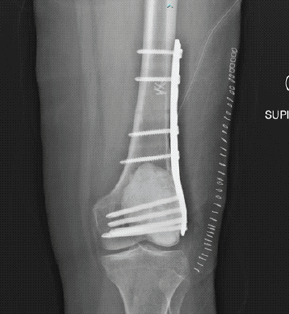

Distal Femur Extension Osteotomy for Fixed Flexion Deformity Following Distal Femur Malunion – A Case Report